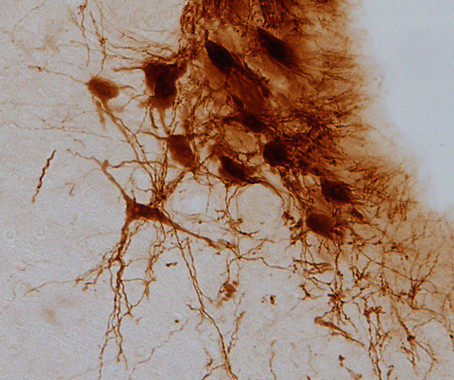

Neuronas de locus cerúleo. / Fundación Descubre

Sin embargo, este desarrollo se manifiesta en el cerebro mediante procesos diferentes. Cuando el dolor se origina por una diabetes mal controlada, este se refleja en el sistema nervioso central a través de una disminución en la producción de noradrenalina y una disfunción en la actividad del locus cerúleo, una región anatómica en el tallo cerebral involucrada en la respuesta al pánico y al estrés.

El locus cerúleo es el principal productor de noradrenalina del cerebro, una biomolécula involucrada en la transmisión del mensaje nervioso entre las neuronas y que desempeña un papel importante en la ansiedad y la depresión.